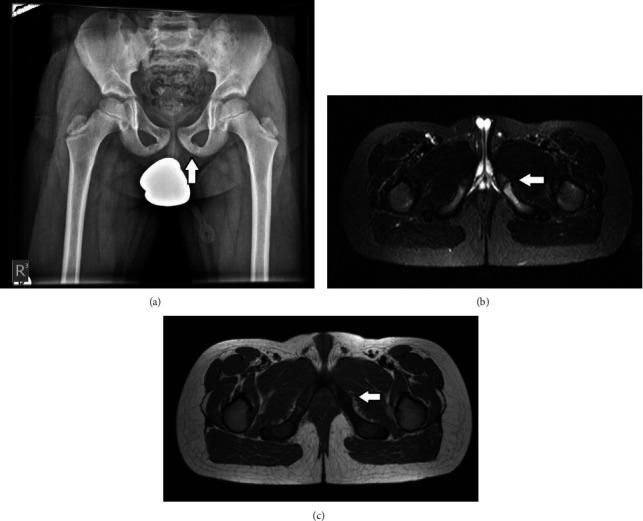

Osteochondritis of the ischiopubic area is a rare disease of children that presents with hip pain and limping. Careful examination and appropriate investigations are essential to establish a definite diagnosis. We report a case series of four children, ages 10-14-year-old, with osteochondritis of the ischiopubic area. Plain X-ray examination showed an area of diffuse irregular calcification of the ischium in two of the children, while in the other two there was an asymmetrical enlargement of the ischiopubic synchondrosis. MRI investigation was the most helpful examination. Bone edema was found in all four children. A calcified mass separated from the host ischium was found in the first two children. The cortex was normal, without irregular destruction. Bone edema of both the ischium and pubic alongside the synchondrosis was found in the following two children, with intact cortices and asymmetrical enlargement. Osteochondritis lesions of the ischium and the ischiopubic area have radiological findings similar to several severe diseases. Bone edema on MRI investigation in children must be properly evaluated. Appropriate radiological examination enabled us to confirm the diagnosis of the osteochondritis and to avoid unnecessary procedures. We want to draw attention to the rare diagnosis of osteochondritis of the ischiopubic area, and the clinical significance, as a cause of hip pain and limping in children.

坐骨耻骨区骨软骨炎是一种罕见的儿童疾病,表现为髋关节疼痛和跛行。仔细检查和适当的检查对于明确诊断至关重要。我们报告了一组4例年龄在10 - 14岁的患有坐骨耻骨区骨软骨炎的儿童病例。X线平片检查显示,其中2例儿童坐骨有弥漫性不规则钙化区域,而另外2例坐骨耻骨联合不对称增大。MRI检查是最有帮助的检查。所有4例儿童均发现骨水肿。前2例儿童发现有与宿主坐骨分离的钙化肿块。皮质正常,无不规则破坏。后2例儿童在耻骨联合旁的坐骨和耻骨均发现骨水肿,皮质完整且不对称增大。坐骨和坐骨耻骨区的骨软骨炎病变有类似于几种严重疾病的影像学表现。儿童MRI检查发现的骨水肿必须进行恰当评估。适当的影像学检查使我们能够确诊骨软骨炎并避免不必要的操作。我们希望引起对坐骨耻骨区骨软骨炎这一罕见诊断及其作为儿童髋关节疼痛和跛行原因的临床意义的关注。